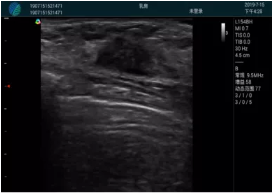

病例二:

腺體內(nèi)部清晰顯示一低回聲塊影,形態(tài)不規(guī)則,邊界模糊,邊緣呈毛刺狀,內(nèi)部見砂礫樣鈣化

M20引導(dǎo)下穿刺活檢術(shù)

M20引導(dǎo)下平面內(nèi)穿刺取出的腫塊組織